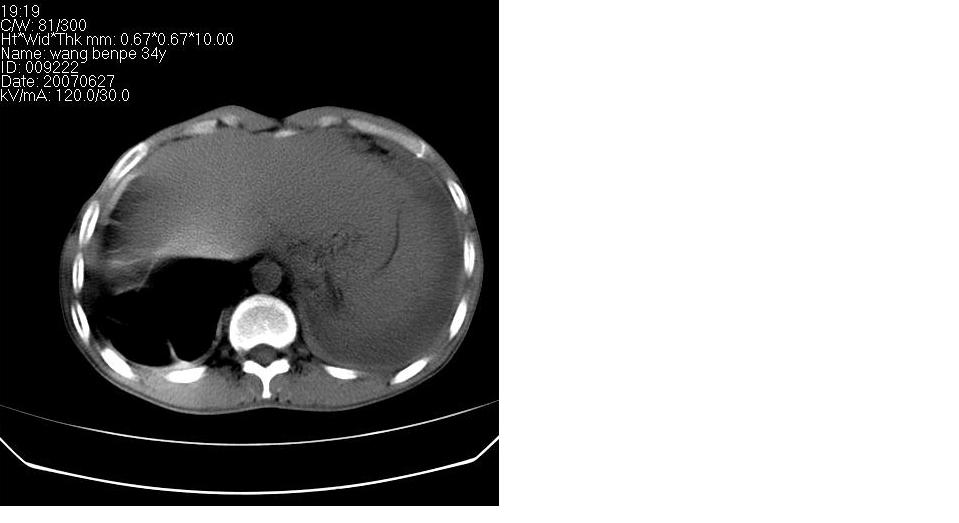

以下是引用苯小孩在2007-6-27 15:09:00的发言:[br]考虑:1、右肺继发性肺结核.2、双侧包裹性积液<胸腔及叶间>3、双侧局部胸膜增厚.[br]建议胸水化验检查.

以下是引用yanghaochen88在2007-6-27 15:08:00的发言:[br]双肺上野散在粟粒状影、包裹性积液、胸膜增厚粘连、叶间积液---tb,至于分型还得结合病史体征细究妥当些。

以下是引用zjzjr在2007-6-27 16:49:00的发言:[br]肺结核、结核性胸膜炎。